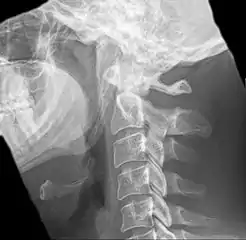

![]() | |

| Anteroposterior and lateral radiographs of cervical spine showing ossification of the stylohyoid ligament on both sides | |

Radiograph, lateral view showing elongated stylohyoid process and stylohyoid ligament ossification

Radiograph, lateral view showing joint-like formation in ossified stylohyoid ligament